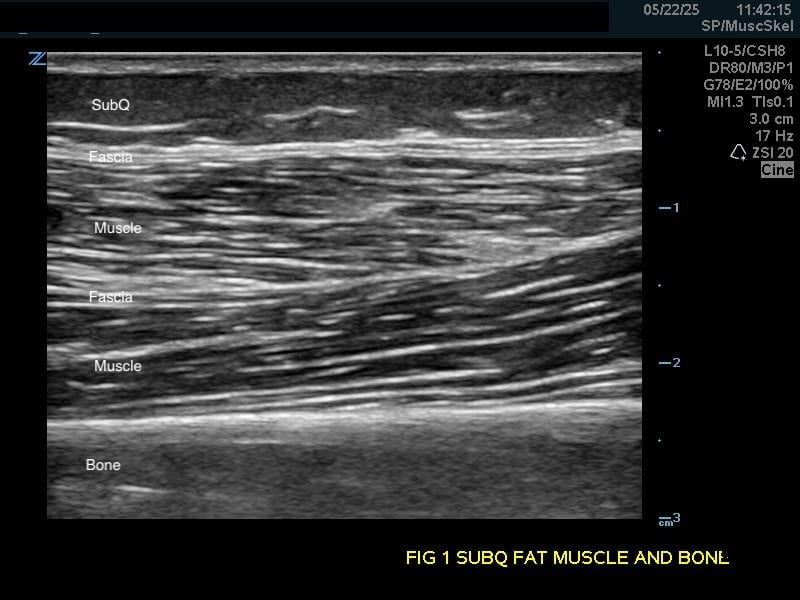

Figure 1b.

Transverse view.

Subcutaneous fat: Relatively hypoechoic with thin septations of connective tissue. The thickness of this layer varies and may require increasing the depth setting of your machine.

Muscle: Longitudinally, appears as slabs of striated hypoechoic tissue contained within the thin hyperechoic lines of fascia. Viewed transversely, muscle striations or septa appear dotted and punctate or form short lines. Fascial lines separate muscle compartments.